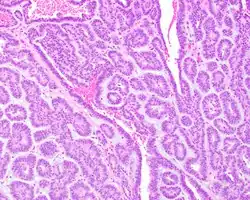

A hematoxylin and eosin stained slide of canalicular adenoma showing multifocality

Canalicular adenoma growths are usually small at the time they are noticed, with an average size of about 1.6 cm.[1] Their histologic appearance is very distinct, with a channel-like pattern between cords and ribbons; the pattern has been described as resembling a "string of pearls."

A hematoxylin and eosin stained slide of canalicular adenoma showing large canaliculi

A hematoxylin and eosin stained slide of canalicular adenoma showing beading